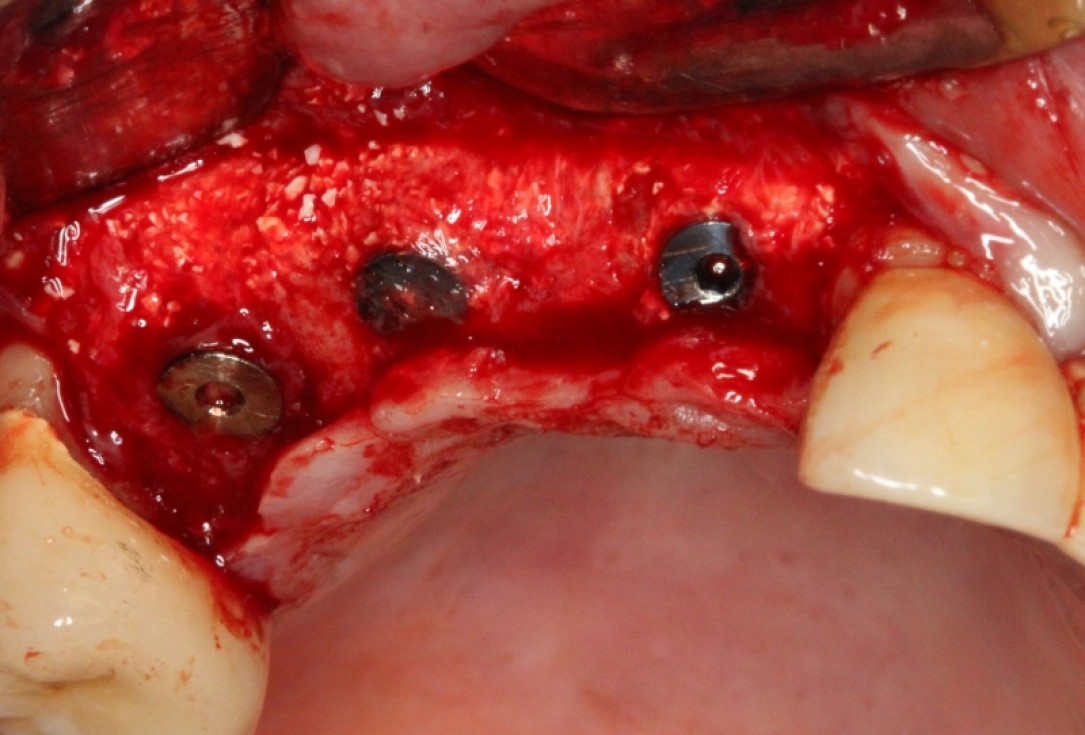

Implant insertion in atrophic alveolar ridge